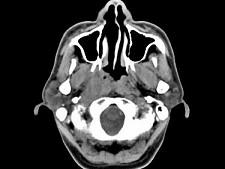

男,52岁,血涕3月余。CT如图所示,最可能的诊断为 ( )A、小唾液腺瘤B、咽旁脓肿C、咽旁混合瘤D、咽部神经纤维瘤E、鼻咽癌

问题 男,52岁,血涕3月余。CT如图所示,最可能的诊断为 ( )

选项 A、小唾液腺瘤 B、咽旁脓肿 C、咽旁混合瘤 D、咽部神经纤维瘤 E、鼻咽癌

答案 E